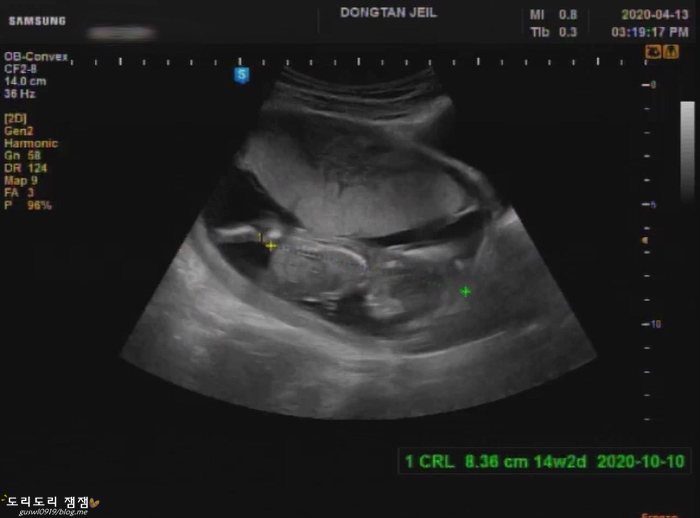

조직 검사가 끝나면 검사 결과도 걱정입니다만, 뱃속의 복권이 걱정이 되었습니다.~ 금방 끝난 검사인데 너무 긴장해서 ㅠㅠ (긴장해서 손에 땀이…) 그래서 바로 위 산부인과에서 초음파를 봤어요.

다행히 아기는 열심히 움직이고 있었어요!너무 뛰어서 심장 소리를 듣기가 힘들었어요.아마 아기도 조금은 스트레스를 받은 것 같아요.TT 그래도 심장도 뛰는 모습을 봐서 정말 다행이에요.

정말 너무 열심히 움직이더라고요 밑에 코 킁킁, 꿈틀꿈틀!www

원래는 4주 후에 만나는 복순이였는데 이렇게 2주에 다시 만나고 왔어요.^^ ww

아!! 그리고 한 가지 더 말씀드리자면!!이렇게 정기 검진이 아닌 초음파로 보는 경우는 보통 초음파 가격입니다.바우처 카드는 사용 가능하지만, 3만원 정도의 초음파 비용이 발생합니다!!